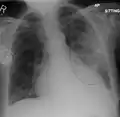

AP CXR showing left lower lobe pneumonia associated with a small left sided pleural effusion